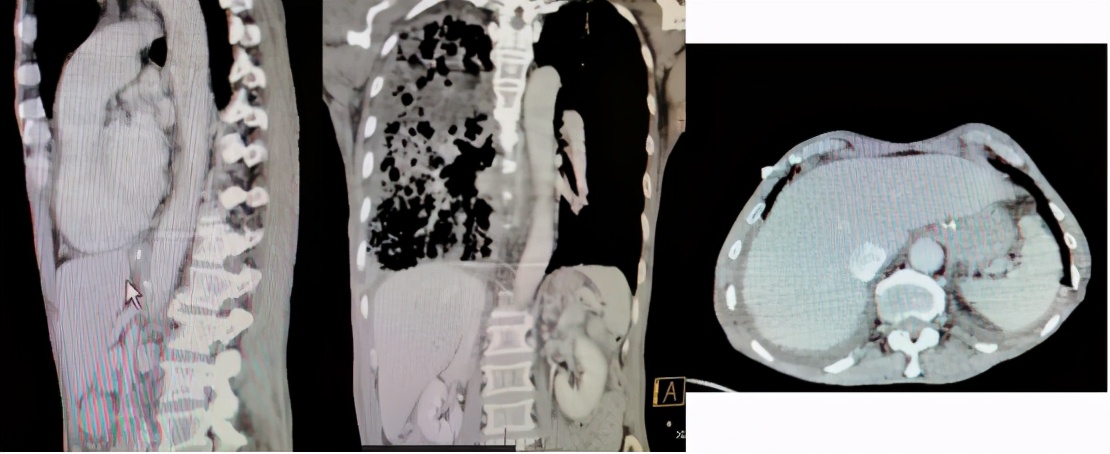

「疑犯」渐渐浮出水面,但如何用进一步检查、诊治及随访等手段帮助「定案」? 首先,我们完善了胸腔积液常规检查,积液呈乳白色,浑浊,有凝块,白细胞(+),红细胞(+++),多核细胞80%,单核细胞20%;随即完善了胸腔积液生化检查显示为:TP 22.3g/L,ALB 14.8g/L,LDH 249IU/L;支气管分泌物pH 8~9;支气管分泌物涂片偶见颗粒状黄色结晶,并将此分泌物做胆红素干化学试验示阳性,考虑此结晶为 胆红素颗粒状结晶 ;支气管分泌物培养(7月24日):洋葱伯克霍尔德菌,鲍曼不动杆菌(药敏:替加环素中介,余耐药);血、胸腔积液、支气管分泌物结果如下(表2);肝胆CT+增强(图5):肝脾胰腺、双肾形态正常,未见明显异常密度及异常强化灶,胆囊未显示,胆囊区见不规则金属密度影,未见腹水征。

图5:肝胆CT+增强(7月20日)